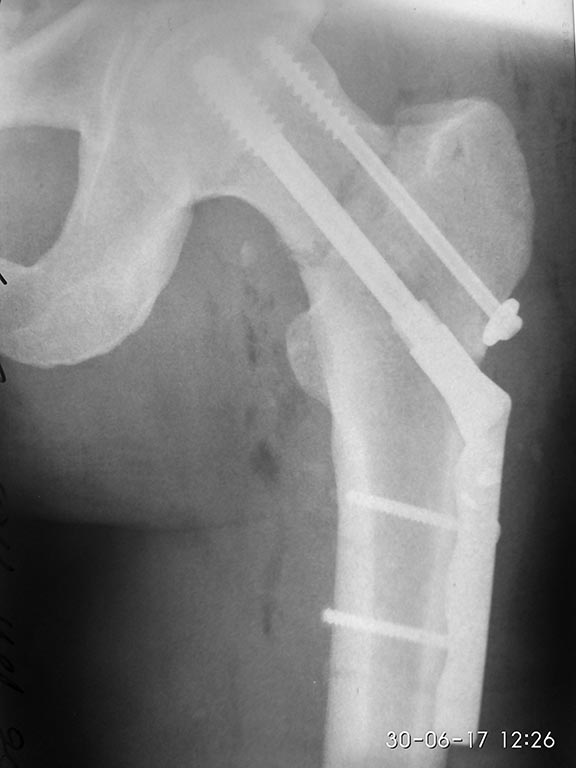

[Ortho] Подскажите оптимальную тактику - перелом шейки бедра при политравме

Пока только фас. Бок технически не получилось (АВФ бедро-голень на

уровне колена). Профиль С ЭОПа.